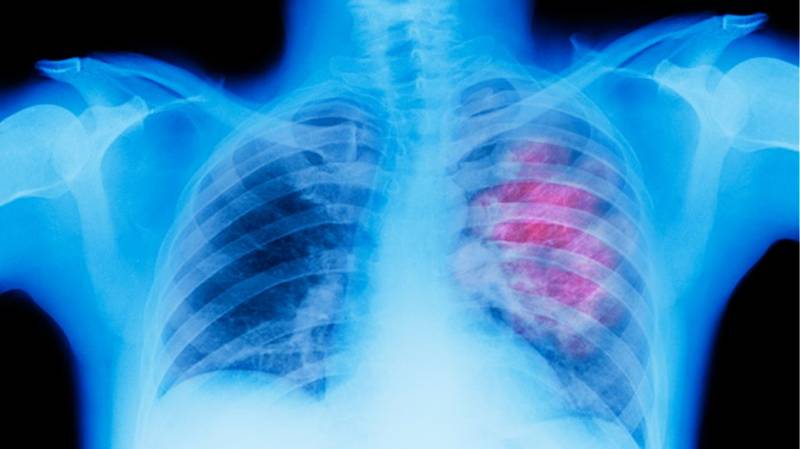

Ο καρκίνος του πνεύμονα συνεχίζει να παραμένει σε χαμηλά επίπεδα 5ετούς επιβίωσης που κυμαίνονται στο 20% σε σχέση με τους υπόλοιπους τρεις πιο συχνούς καρκίνους (μαστό, παχέος εντέρου και προστάτη).